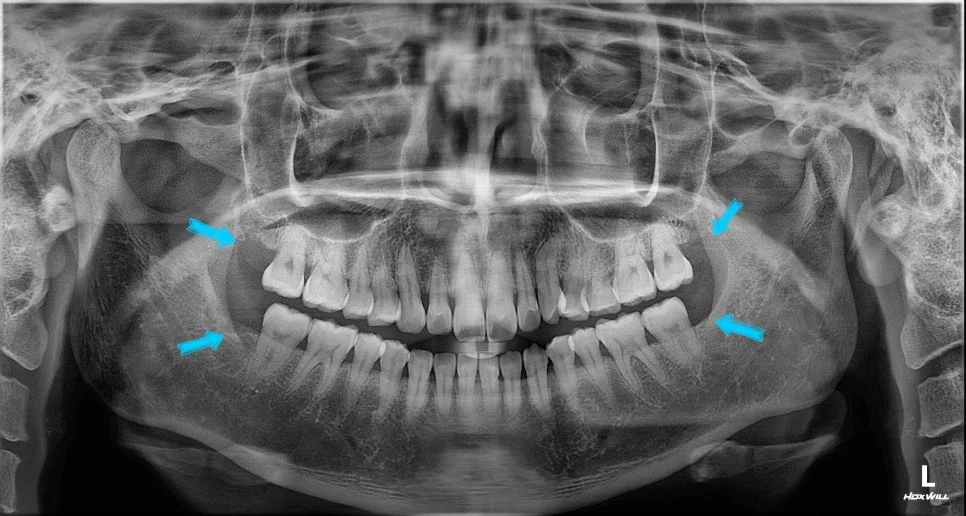

파노라마 X-ray — 발치 전 전체 확인

파노라마 X-ray — 상하 양쪽 사랑니 4개 위치 (파란 화살표)

발치 결과 — 상악 양쪽

발치 결과 — 하악 양쪽 (제2대구치 보존 확인)

무엇보다 제2대구치 역시 손상 없이 잘 보존되었습니다. 이 부분이 가장 중요한 체크포인트였죠.

잔여 뿌리 없이야 발치가 잘 되었다고 볼 수 있습니다.

이런 사후 X-ray는 수술이 정확하게 끝났는지 검증하는 핵심 자료라 꼭 확인해야 하는 단계이기도 합니다~